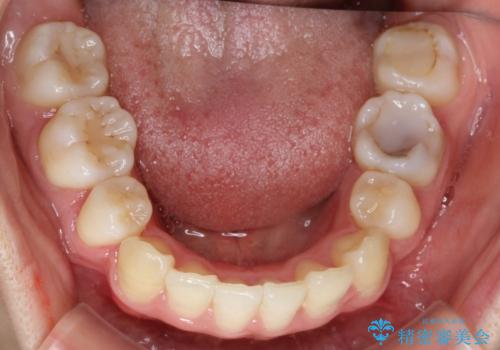

- 八重歯と前歯のガタガタを主訴に来院されました。

目立たない装置をご希望でしたので、上下左右の歯を1本ずつ抜歯してハーフリンガルでの矯正を行いました。